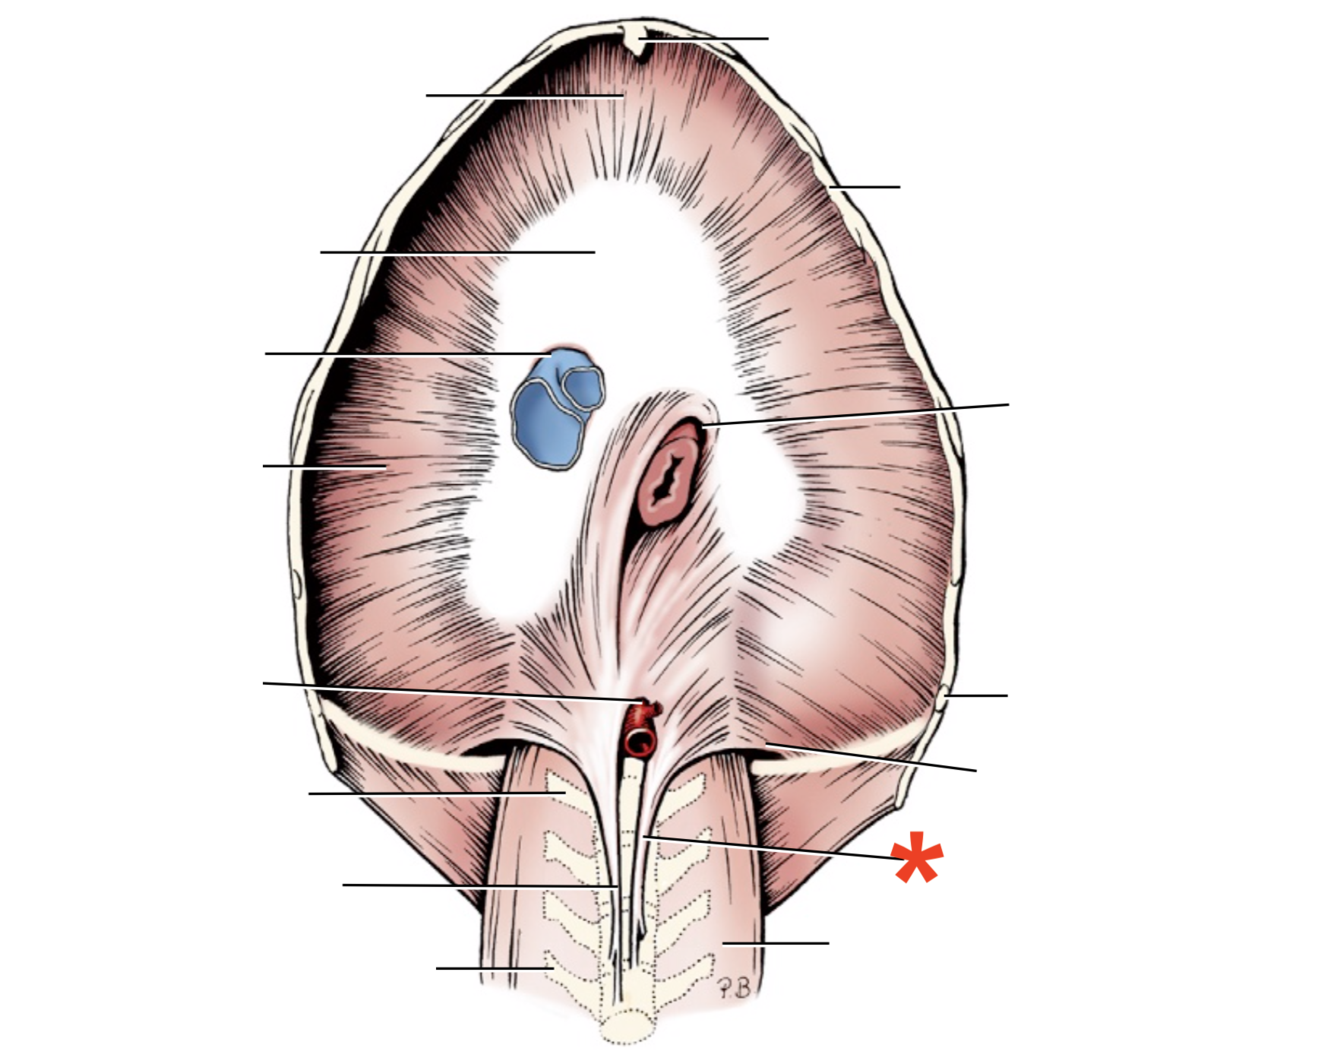

Name given to the most cranial part of the diaphragm.

Cupula Diaphragmatis

Q

Pars sternalis

Q

Foramen vena cavae

Q

Pars costalis

Q

Hiatus aorticus

Q

Arcus lumbocostalis

Q

Hiatus oesophagus

Q

Crus sinistrum

Q

Crus dextrum

Q

Centrum tendineum

Q

Corona muscularis